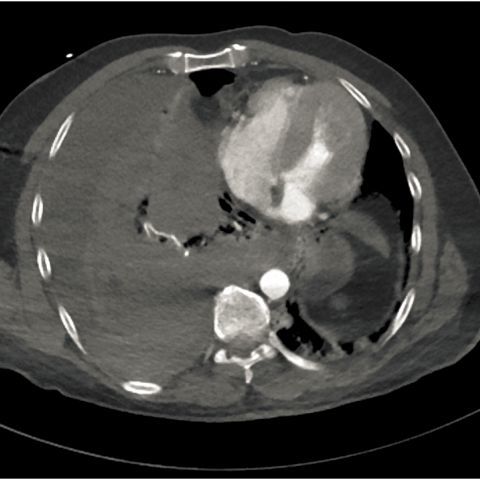

【病例讨论】突发右侧大量血胸,值得讨论下.(刚进来的新病人).

大量自发性血胸你见过吗│以影识病

特发性自发性血胸及壁层胸膜下血肿一例